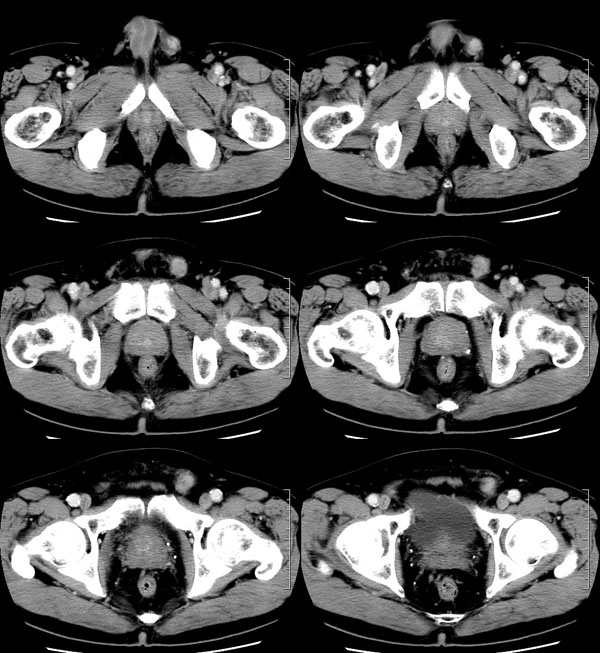

| 男性,69岁。自2个月前开始无意中发现左侧阴囊内一鸡蛋大小肿物,当时无伴疼痛等不适,未予重视。肿物逐渐增大,近段时间常伴左会阴部、腹股沟区牵扯不适,并于2周前在我院门诊行彩超检查提示“左侧附睾肿瘤可能,左侧睾丸鞘膜积液”。 专科检查:左侧阴囊肿大,其内可触及一鹅蛋大小肿物,表面光滑。肿物前部呈囊性感,后部质硬,按压无疼痛,无缩小,活动度良好。左侧睾丸未触及,透光试验(±)。                 王仕学发言:左侧睾丸见一密度不均肿块,边缘清楚,周围见水样密度影;考虑睾丸生殖细胞性肿瘤可能性大. 睾丸肿瘤占生殖系统肿瘤的3%-5%,占男性恶性肿瘤的0.5%-1.0%,其中生殖细胞性肿瘤占95%.睾丸肿瘤包括生殖细胞和非生殖细胞肿瘤两大类,前者占95%以上,后者不到5%.非生殖细胞肿瘤虽少见,但种类繁杂,主要有支持细胞、间质细胞和支持细胞-间质细胞瘤等功能性肿瘤,和间皮瘤、腺癌、横纹肌肉瘤、粘液性囊腺瘤、纤维上皮瘤、黑素神经外胚瘤、淋巴瘤等附属组织肿瘤。不同的病理类型的睾丸肿瘤发病率高峰不同,睾丸癌多发于35岁以前,精原细胞瘤发病高峰为30-35岁。精原细胞瘤约占睾丸肿瘤的60%,发病高峰在30-35岁。85%的患者睾丸有明显肿大,肿瘤局部侵犯力较低,肿瘤一般有明显界限。 手术:行“左侧附睾、睾丸、精索切除术”。 病理诊断:(左睾丸、附睾)肿物,为低分化腺癌。另送检(左精索远端)肿物,镜下亦为低分化腺癌。 免疫组化:ck(l)(++++)、cea(+++)、ca19-9(-)、psa(-)、plap(-)、p53(-)、vimentin(-)。 原贴地址:http://www.radinet.com.cn/forum_view.asp?forum_id=4&view_id=30707 |